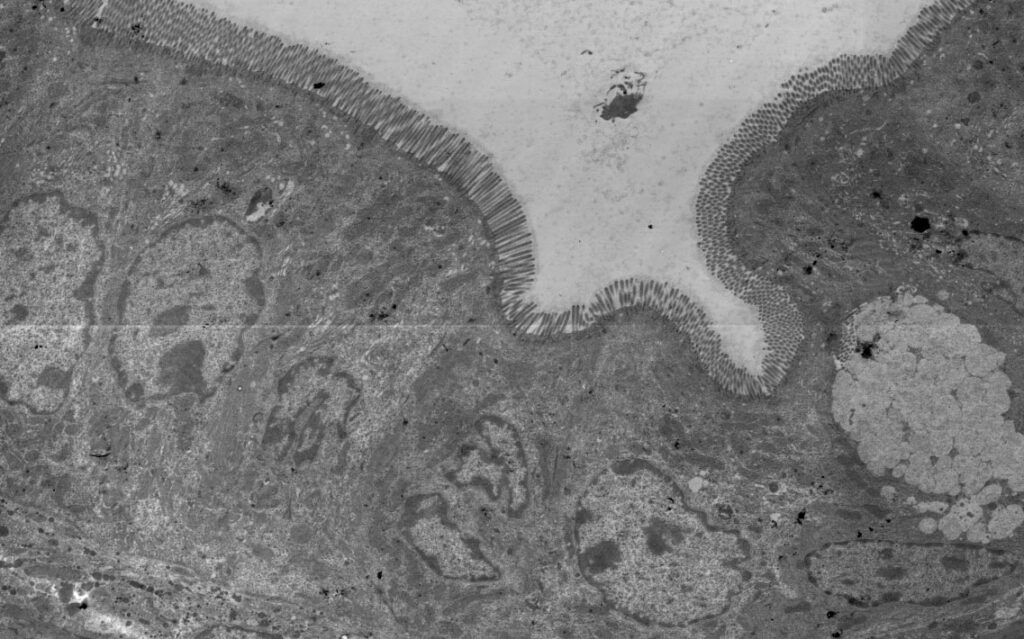

Beschädigung der Darmbarriere

Eine weitere Schlüsselkomponente ist die Darmbarriere, eine Schutzschicht, die verhindert, dass schädliche Substanzen und Mikroorganismen in den Körper gelangen. Bei CED kann diese Barriere beschädigt sein, was es erleichtert, dass Bakterien und deren Bestandteile in die Darmwand eindringen und dort eine Immunreaktion auslösen. Dieser Vorgang kann die Entzündung weiter vorantreiben und die Symptome verschlimmern.